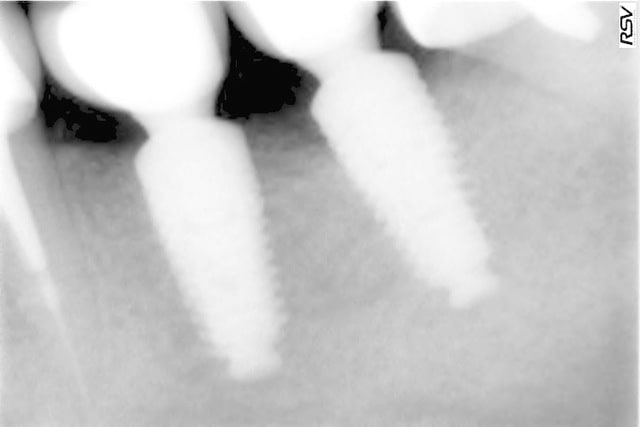

tous mes implants sont ostéo-intégrés, mais je trouve que la cratérisation est très importante et surtout très rapide.

donc pour moi, il y a un problème même si le taux de succès est de 100% en 2 ans.

voici les radios le jour de la pose

le krestal doit être en crestal et non en infra-osseux: il s'agit d'une connectique à plat et non d'un cône morse.

as-tu constaté une différence en ce qui concerne les cratérisations entre ceux posés en un temps et ceux en 2 temps ?

il me semble que sur le 1° cas présenté,la partie biseautée de l'implant est enfouie et que la cratérisation est nulle, idem pour l'implant mésial du dernier cas.

Sur son site Tekka préconise de mettre la partie supérieur de l'implant en juxtacrestal , donc le biseau est infraosseux...

Tu remarqueras que le biseau mésial de l'implant mésial qui a été correctement enfoui n'a pas bronché.